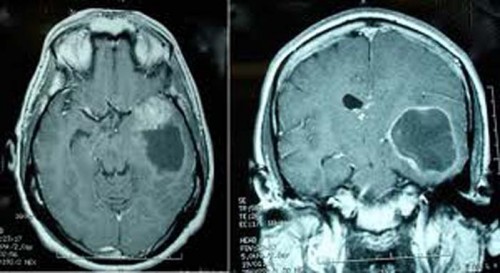

Сьогодні в Ужгороді розпочала свою роботу Міжнародна науково-практична конференція «Актуальні питання нейроонкології». Майже півтори сотні радіологів, рентгенологів, нейрохірургів та невропатологів з України, Угорщини, Словаччини і Білорусії зібрались, щоб обговорити сучасні можливості магнітно-резонансної томографії та комп’ютерної томографії у діагностиці онкологічних захворювань головного та спинного мозку дітей та дорослих. Окремо йтиметься про сучасні методики лікування онкопатологій . В рамках конференції передбачено низку круглих столів та панельних дискусій.

Фахівці-медики та науковці ділитимуться своїм досвідом та вивчатимуть напрацювання колег у діагностиці та хірургічному лікуванні внутрішньо мозкових пухлин та пухлин нервової системи.